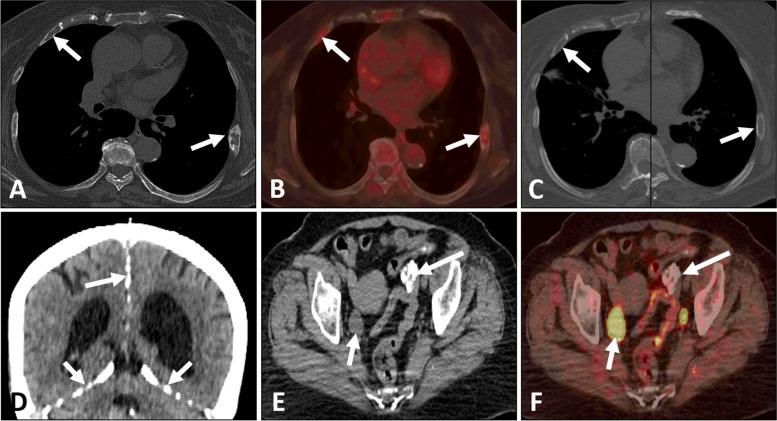

A 71-year-old woman with the left invasive breast cancer was treated with hormone therapy for six months and underwent the F-FDG PET/CT examination for efficacy evaluation. F-FDG PET/CT revealed the improvement after treatment and other unexpected findings, including multiple nodules on the skin with F-FDG uptake, bone expansion of cystic lesions in the bilateral ribs, ectopic calcifications and dilated right ureter. She had no known family history. Then, the patient underwent surgical excision of the all skin nodules and the postoperative pathology were multiple basal cell carcinomas. Finally, the comprehensive diagnosis of NBCCS was made. The patient was still in follow-up. Additionally, we have summarized the reported cases (n = 3) with F-FDG PET/CT from the literature.

一名 71 岁女性患有左侧浸润性乳腺癌,接受了六个月的激素治疗,并进行了 F-FDG PET/CT 检查以评估疗效。F-FDG PET/CT 显示治疗后有所改善,同时还发现了其他意外发现,包括皮肤多处结节伴有 F-FDG 摄取、双侧肋骨囊性病变的骨膨胀、异位钙化和右侧输尿管扩张。患者无已知家族史。随后,患者接受了所有皮肤结节的手术切除,术后病理为多发性基底细胞癌。最终,综合诊断为 NBCCS。患者仍在随访中。此外,我们还总结了文献中报道的 3 例(n=3)伴有 F-FDG PET/CT 的病例。